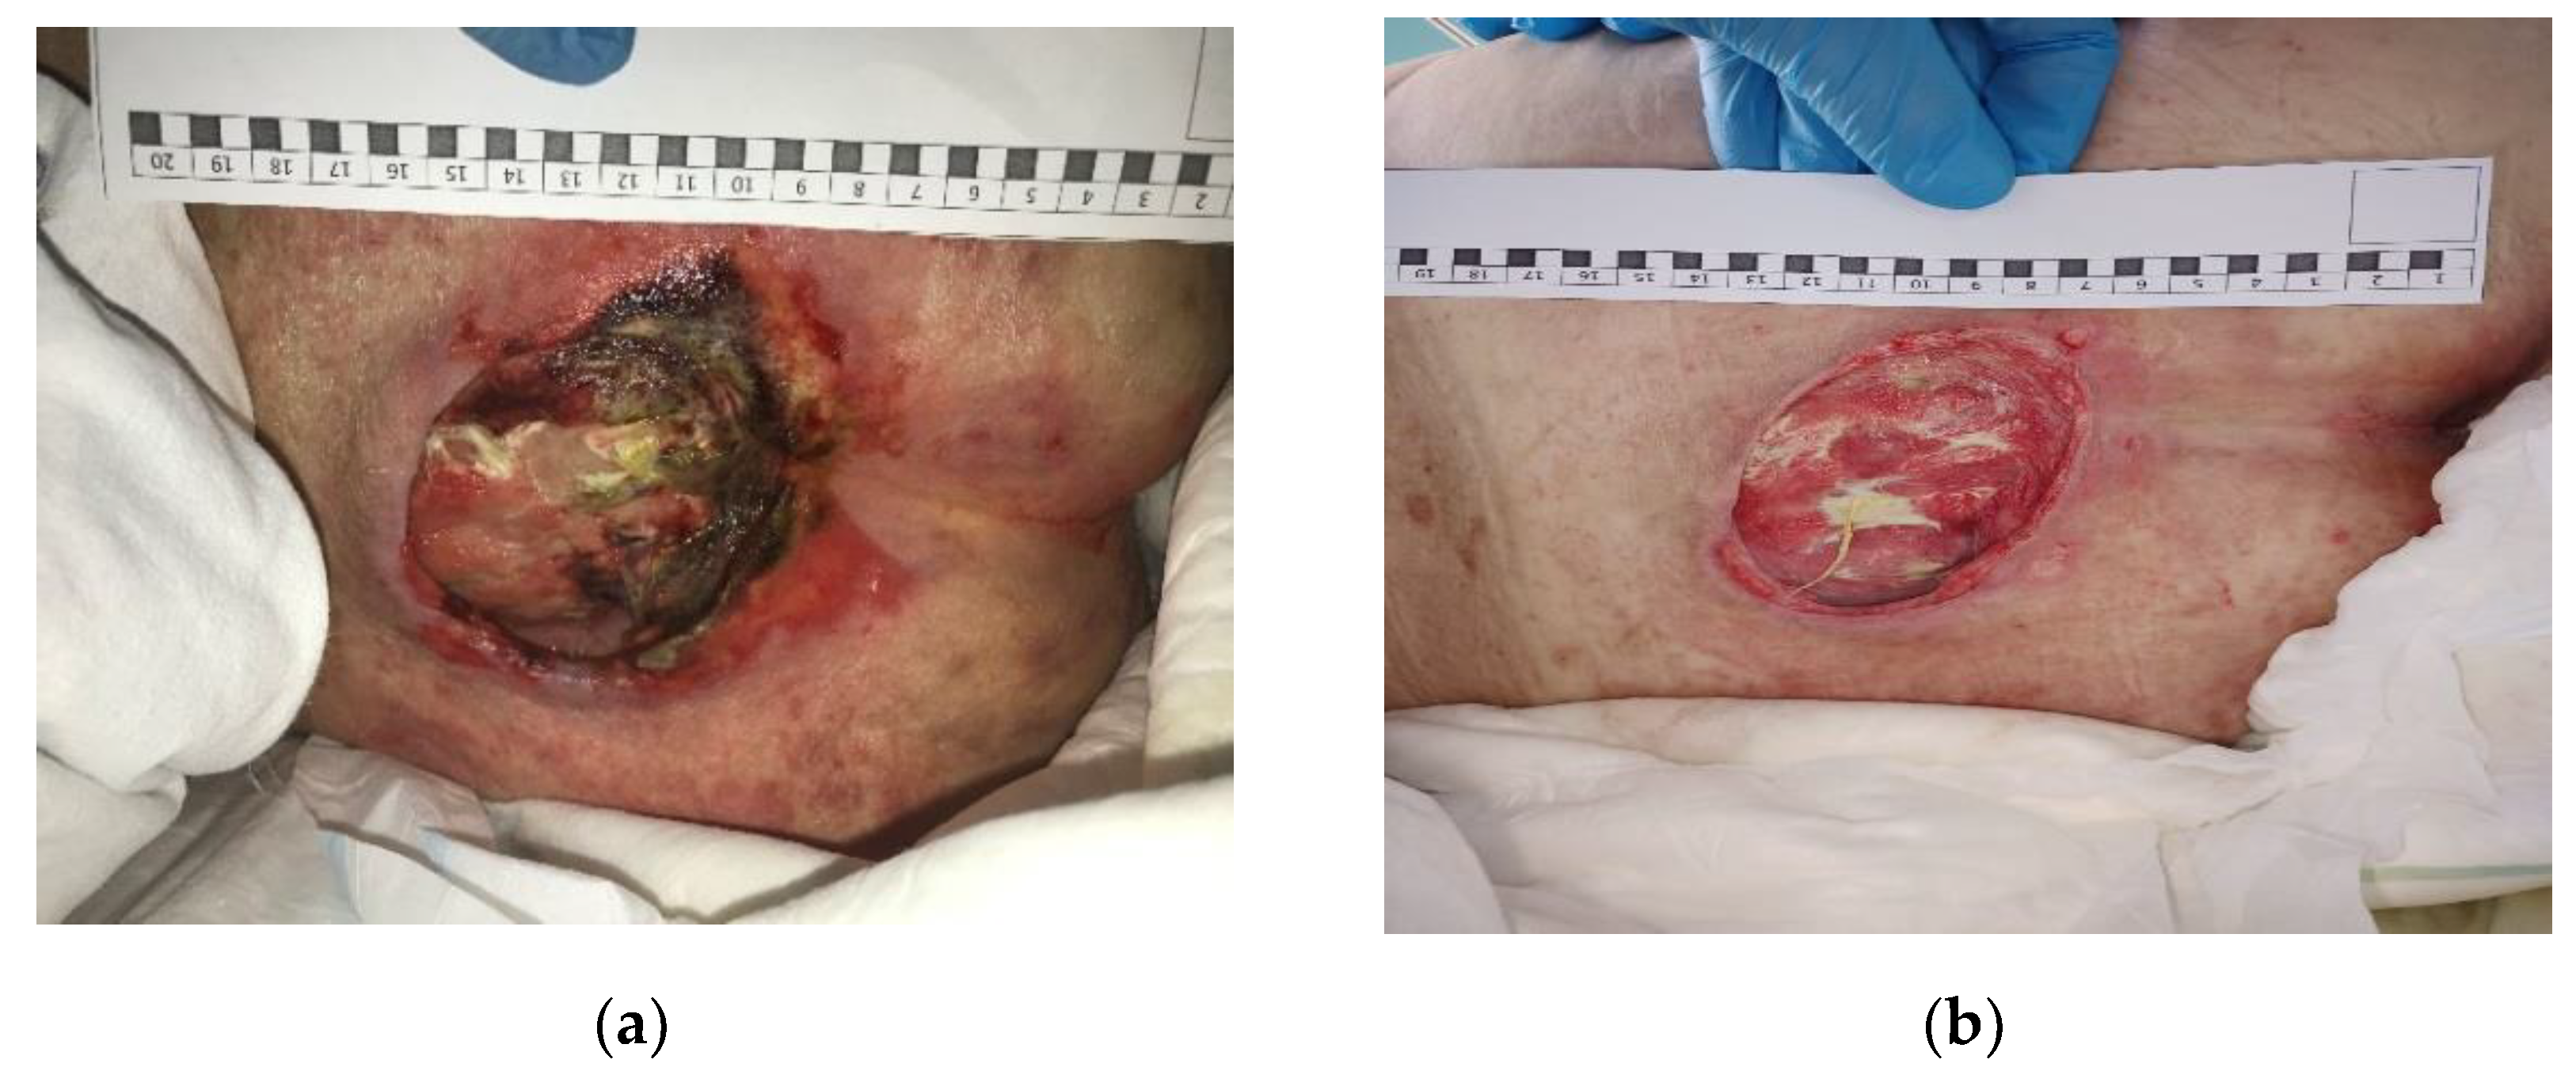

3.2. Clinical Research

3.3. Morphological Studies